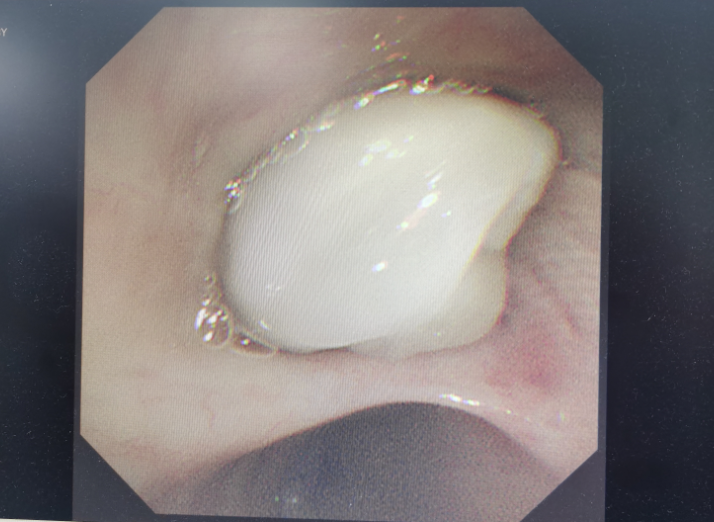

四个月前,谢师傅因咳嗽、发烧来到武汉市肺科医院就诊。医生发现他的右上肺因实变而消失,于是通过气管镜一探究竟。气管镜探查到右上肺支气管的管口时发现,有一乳白色巨大新生物,将右上支气管死死堵住。